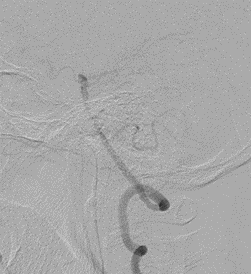

左侧瘤体形态欠规则,4mm×30mm Streamline 优先处理左侧动脉瘤

术后3月复查,瘤体未见显影,载瘤动脉通畅

同期4mm×20mm Streamline 进一步处理右侧动脉瘤